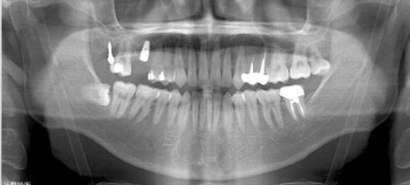

因長期缺失第一大臼齒而導致第二大臼齒歪斜,矯正介入治療將牙齒扶正騰出足夠的空間後 ,再透過植牙將全口重建。

患者全口X光

治療前

治療後